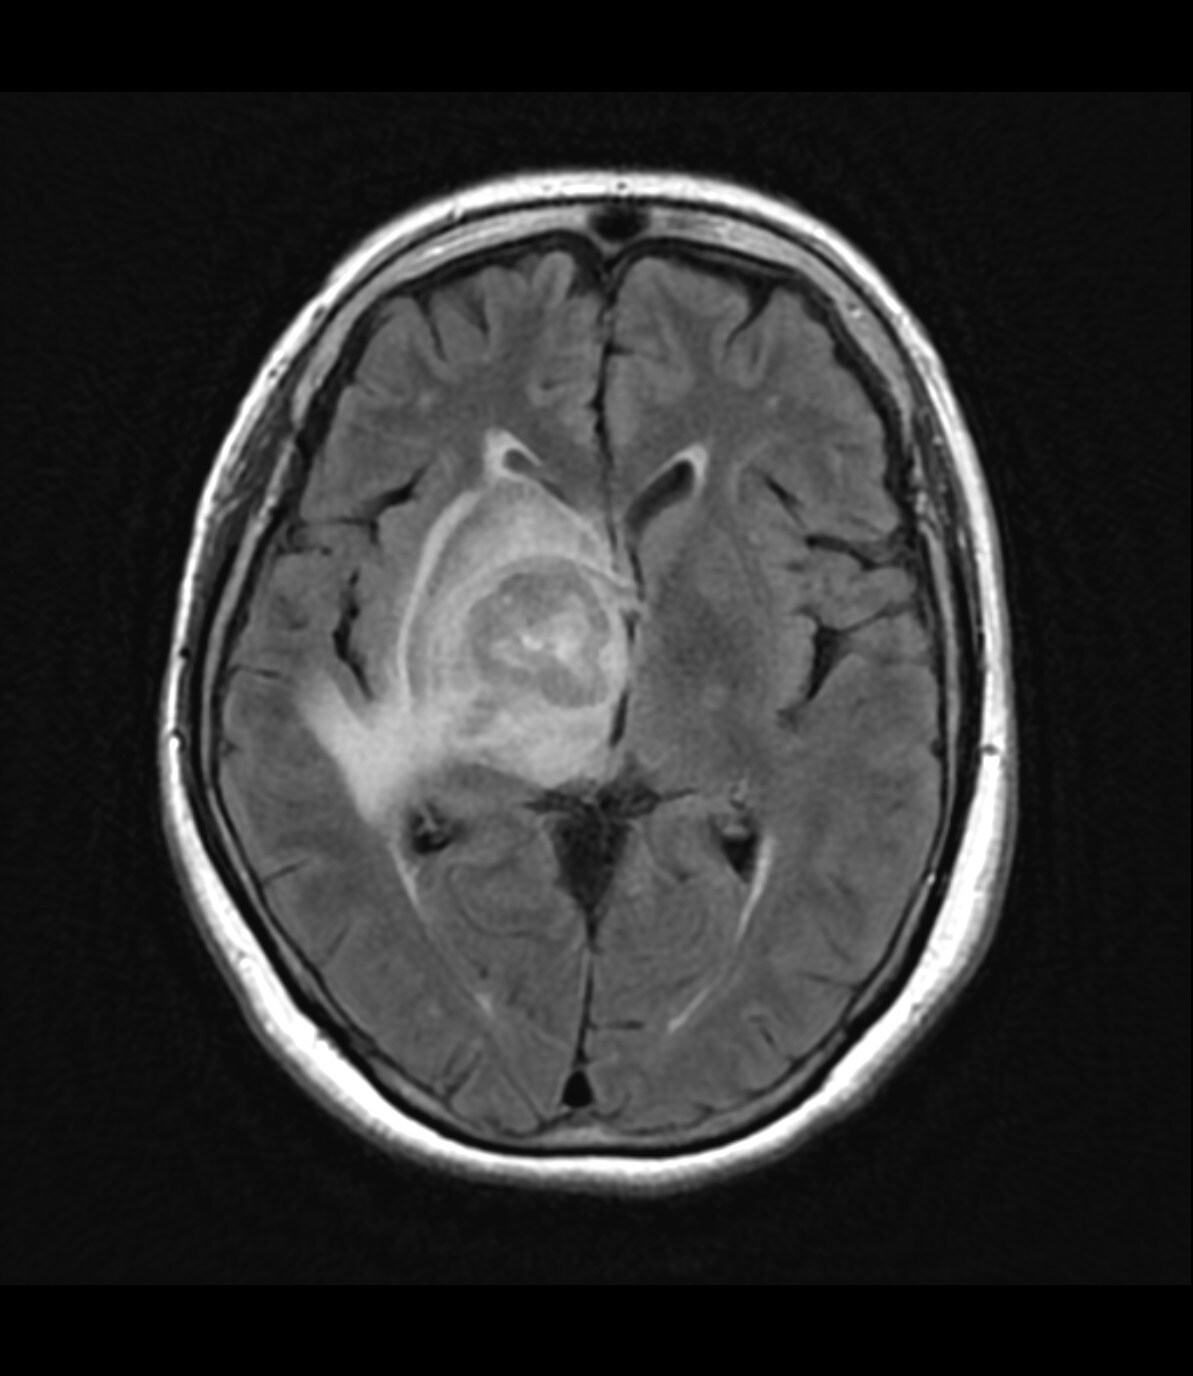

右基底核~視床~右中脳腹側にかけて均一で強いリング状増強効果を呈する腫瘤を認める。周囲に浮腫と思われるFLAIR 高信号域を認める。主病変の濃染部分はFLAIR等信号、DWI 高信号、ADCmap 低信号を呈している。MRS(TE=144)でChoが上昇、CrとNAAが低下している。ASLでは血流の顕著な上昇は認めない。中枢神経原発悪性リンパ腫(PCNSL)が疑われた。脳腫瘍生検の結果、中枢神経原発悪性リンパ腫(PCNSL)と診断された。

造影MRIにより腫瘍の範囲を正確に確認でき、腫瘍生検を行う際に病変を的確に捉えることができるようになると思われる。本症例のように浮腫を伴う脳腫瘍の場合、単純MRIのみでは浮腫と腫瘍の境界が不明瞭であり、腫瘍の範囲を把握するために造影MRIが必要と思われる。